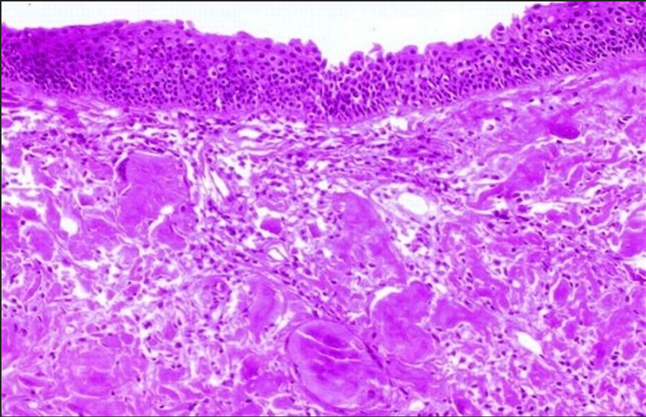

Routine haematological and biochemical profiles were within normal limits. Given the clinical suspicion of a submucosal neoplasm, the patient was taken up for direct laryngoscopy with micro laryngeal excision using CO₂ laser. Meticulous dissection was performed to achieve complete removal of the deposits while preserving the integrity of the vocal ligament and adjacent mucosa. The histopathological examination revealed eosinophilic, amorphous, acellular deposits in the subepithelial stroma (Figure 3). Congo red staining demonstrated classic apple green birefringence under polarized light, confirming the diagnosis of amyloidosis (Figure 4).

Figure 3. Histopathological examination showing respiratory epithelium with underlying pink amorphous debris